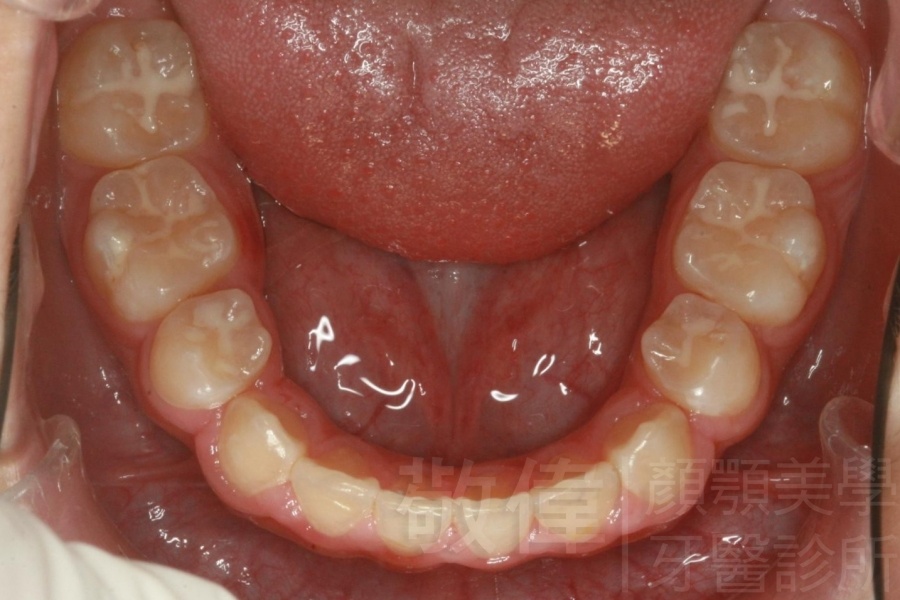

齒顏矯正/上顎暴牙且牙齒極度混亂

矯正前-上   矯正前-下

矯正後-上   矯正後-下

<個案說明>

上顎暴牙且牙齒極度混亂,經由矯正之後,臉型大幅度改善,牙齒的排列更加的整齊健康。相較於之前眼神充滿精神,自信心展現無遺。